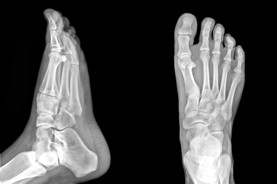

Edmonton Foot Doctor & Foot Physical Therapist

The Foot Institute is an association of Edmonton Doctors specializing in the medical treatment of the foot and ankle, and is one of the largest groups of foot specialists in Alberta.

The Edmonton Foot Institute is dedicated to the medical and surgical treatment of the foot. Our mandate is to provide the best possible medical, surgical and preventative treatment available for our patients. We do this by providing well-trained Doctors who are committed to treat and prevent all types of foot pain, biomechanical disorders, as well as all other problems relating to the feet.

At the Edmonton Foot Institute, our Doctors are trained to specifically treat problems associated with your feet or ankles. Below are several of the most common problems that we see on a day to day basis: